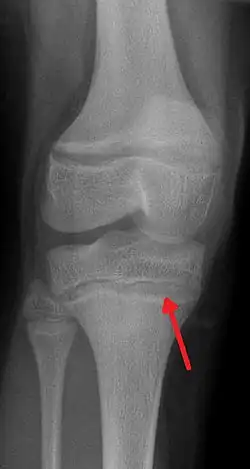

![]() | |

| An X-ray demonstrating the characteristic finding of lead poisoning in humans—dense metaphyseal lines. | |

Blood lead levels are an indicator mainly of recent or current lead exposure, not of total body burden.[212] Lead in bones can be measured noninvasively by X-ray fluorescence; this may be the best measure of cumulative exposure and total body burden.[40] However, this method is not widely available and is mainly used for research rather than routine diagnosis.[106] Another radiographic sign of elevated lead levels is the presence of radiodense lines called lead lines at the metaphysis in the long bones of growing children, especially around the knees.[213] These lead lines, caused by increased calcification due to disrupted metabolism in the growing bones, become wider as the duration of lead exposure increases.[213] X-rays may also reveal lead-containing foreign materials such as paint chips in the gastrointestinal tract.[29][213]